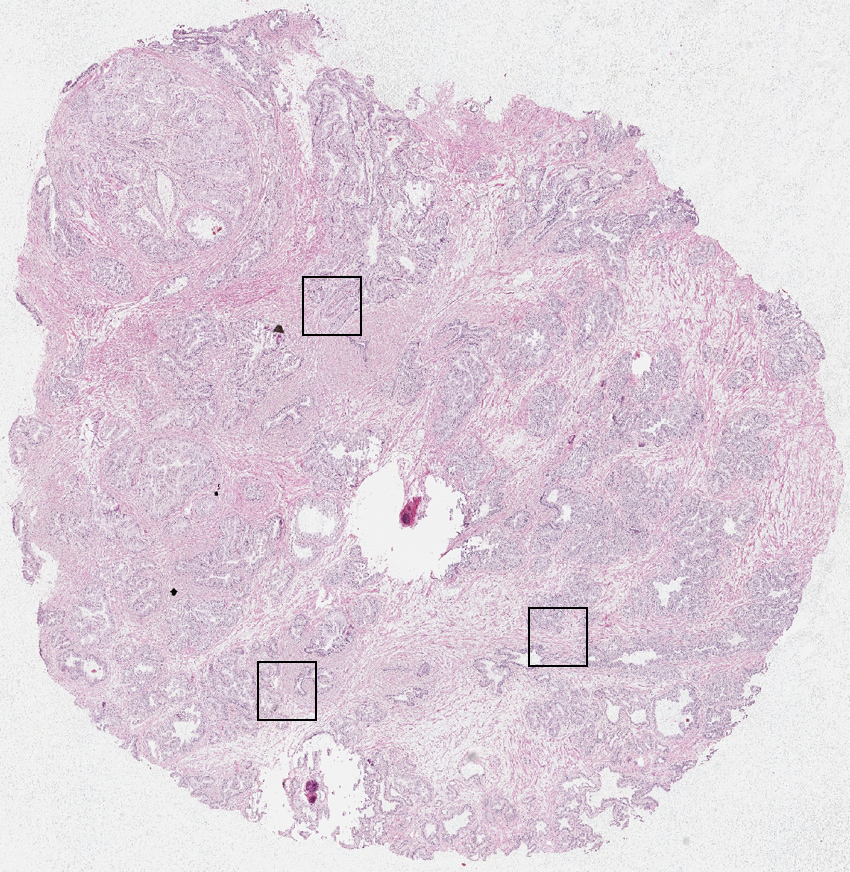

Cell types%

Glandular cells:

65

Smooth muscle cells:

30

Other cell types:

5